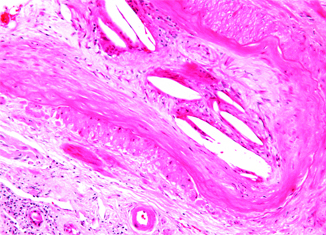

cholesterol

Cholesterol.jpg

Cholesterol rises in the winter

New research finds cholesterol levels rise in the winter